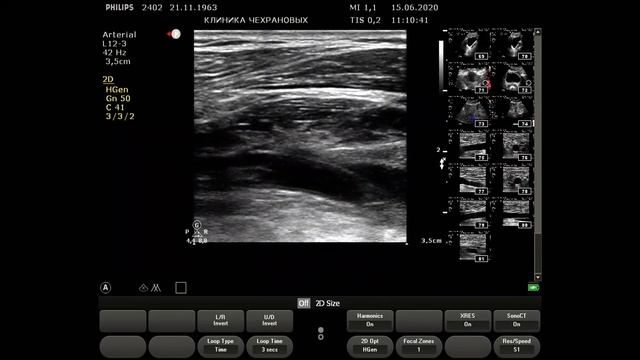

УЗИ сосудов нижних конечностей. Окклюзия бедренных артерий с обеих сторон но почему слева хуже?

ЛПИ слева 04 справа 06. Окклюзия бедренных артерий с обеих сторон но почему слева хуже? Ответ: Есть дополнительный стеноз в НПА слева что не дает ГБА адекватно обеспечить коллатеральный кровоток,